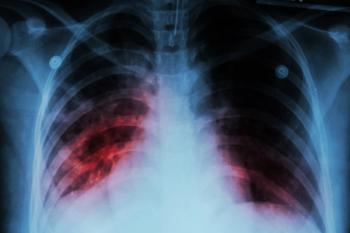

Inhaled corticosteroids were observed to be associated with increases in rates of pneumonia and tuberculosis, according to a recent study.